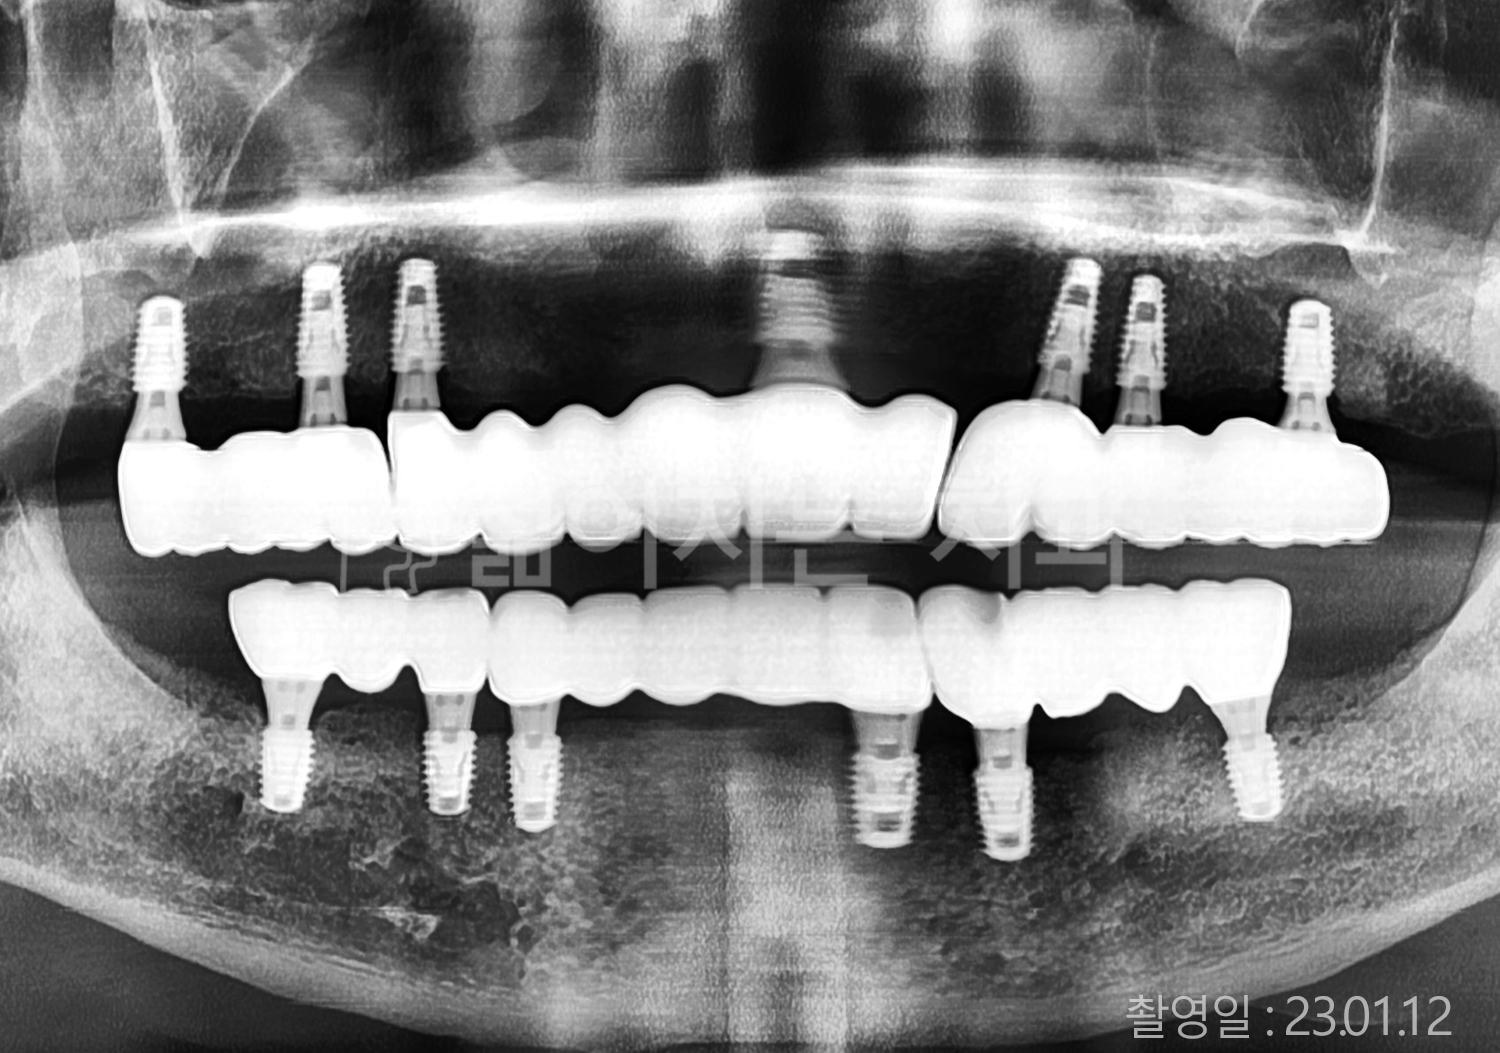

• 70대 고혈압, 고지혈증 전체치아 10개 이상 임플란트

• 60대 당뇨, 간염 전체치아 10개 이상 임플란트

• 80대 골다골증 전체치아 6개 이상 임플란트

• 70대 고혈압, 당뇨 전체치아 10개 이상 임플란트

• 60대 간 질환 전체치아 10개 이상 임플란트

• 60대 전체치아 10개 이상 임플란트

• 70대 전체치아 10개 이상 임플란트